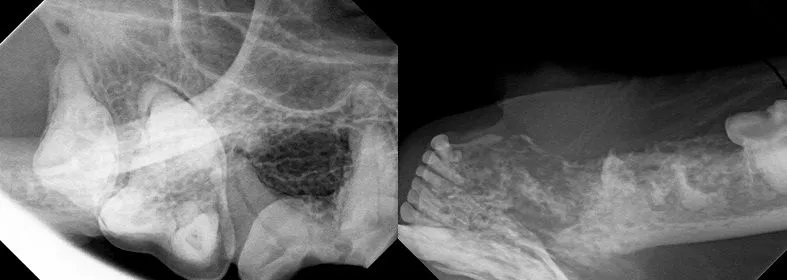

Dental cleanings at Animal Medical Center require general anesthesia. Your pet will be maintained on the safest anesthesia available, monitored with special monitoring equipment and trained staff and kept warm on a circulating hot water blanket. While sleeping, your pet's teeth and mouth will be examined. Their teeth will be cleaned with an ultra-sonic scaler, polished, and treated with fluoride. Dental radiographs will be taken to asses the health of roots and can be utilized to assess other oral diseases.